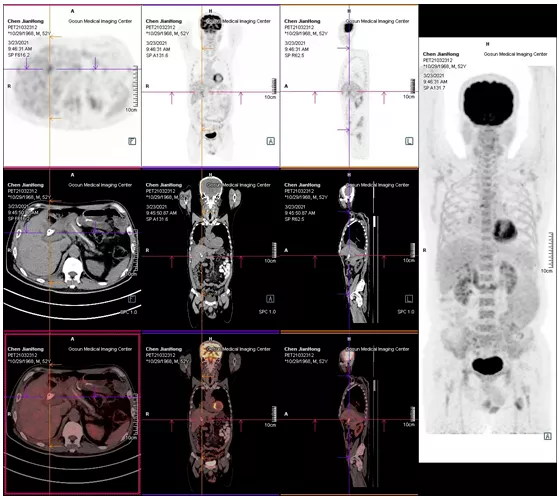

2021年05月 PET/CT檢查結(jié)果

復(fù)查PET-CT提示原術(shù)區(qū)復(fù)發(fā)病灶、肝內(nèi)轉(zhuǎn)移灶、右側(cè)胸膜轉(zhuǎn)移灶控制良好

治療效果評(píng)估

用藥3個(gè)月后,患者精神狀態(tài)明顯好轉(zhuǎn),食欲改善,體重增加,腫瘤指標(biāo)下降,PET/CT結(jié)果提示,無(wú)明顯腫瘤復(fù)發(fā)或轉(zhuǎn)移征象,肝內(nèi)腫瘤活性已受抑制。